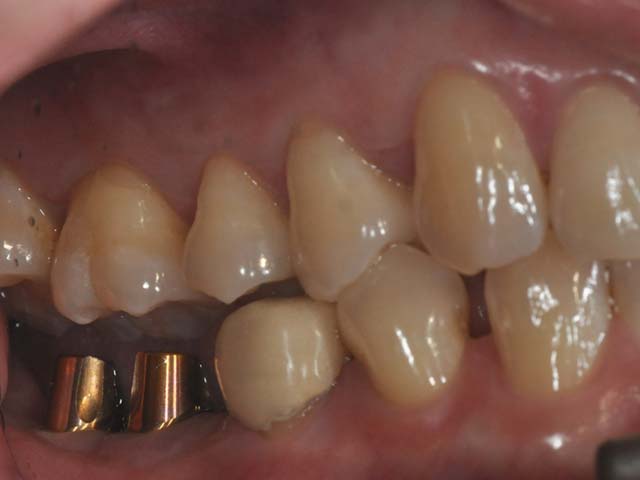

牙橋嚴重蛀牙,即拔即種,避免二次傷口 首頁 案例分享 人工植牙 牙橋嚴重蛀牙,即拔即種,避免二次傷口 多年前製作之牙橋,因為二度齲齒,導致支台齒蛀蝕,而需重新製作 牙橋支臺齒嚴重蛀牙 STEP1.拔除殘根並植入兩根植牙 STEP2.骨粉填補缺損骨頭缺陷 STEP3.三個月後,準備製作正式假牙 STEP4.正式假牙完成